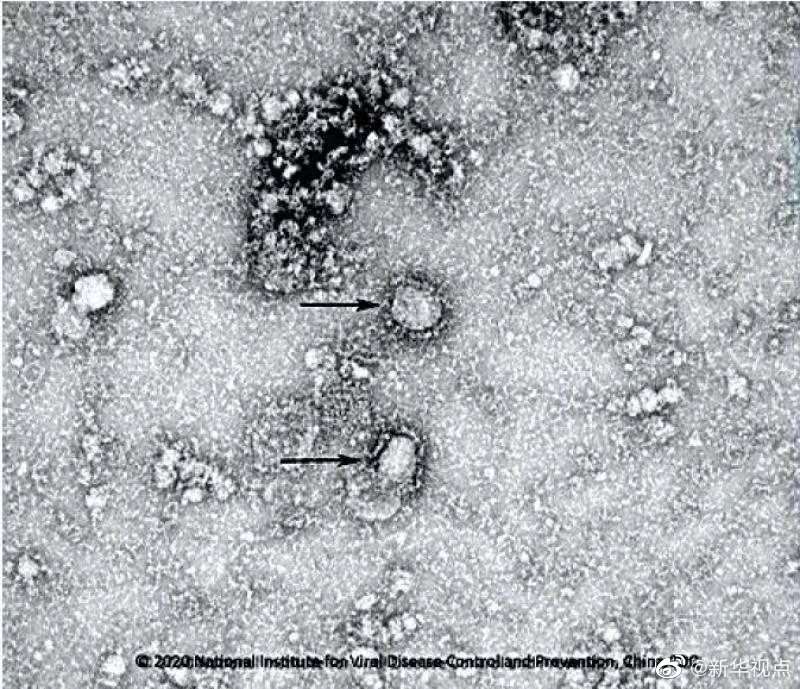

國(guó)家病原微生物資源庫(kù)于2020年1月24日發(fā)布了由中國(guó)疾病預(yù)防控制中心病毒病預(yù)防控制所成功分離的我國(guó)第一株病毒毒種信息及其電鏡照片、新型冠狀病毒核酸檢測(cè)引物和探針序列等國(guó)內(nèi)首次發(fā)布的重要權(quán)威信息,并提供共享服務(wù)??床《尽罢嫒荨薄ㄓ浾咛飼院健⑼醣枺?/p>

好消息!中國(guó)疾控中心成功分離我國(guó)首株新型冠狀病毒毒種,它長(zhǎng)這樣!-新華網(wǎng)